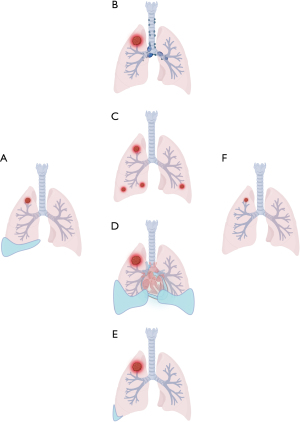

• A chest computed tomography (CT) pattern diagram and proposed diagnostic-therapeutic framework (exploratory, non-validated) are developed to facilitate PsP identification and management.

Chest CT pattern diagram

A CT pattern diagram was developed to visualize typical PsP imaging features (e.g., primary lesion enlargement, metastatic progression, new nodules, paradoxical pleural effusion reduction) based on institutional cases and detailed literature-derived imaging data.

Imaging findings and CT pattern development

The imaging results of the four patients with PsP are presented in Figures 2,3 and Figures S1,S2. Initial radiographic assessment revealed distinct PsP features: primary lesion enlargement (40.0%, 16/40), metastatic lesion progression (60.0%, 24/40), new pulmonary nodules (7.5%, 3/40), and lymph node enlargement (17.5%, 7/40). Notably, two cases (5.0%) demonstrated a paradoxical pattern of primary lesion growth accompanied by pleural effusion reduction—a characteristic yet underrecognized PsP signature.

To systematically categorize PsP manifestations, we developed a chest CT classification system comprising four distinct patterns (Figure 4). The constructed chest CT pattern diagram clearly depicted various imaging features of PsP, providing a visual reference for identifying PsP-related imaging changes.

Our study demonstrates that PsP exhibits diverse imaging patterns, with primary lesion enlargement (40.0%) and metastatic progression (60.0%) being the most prevalent, followed by lymph node enlargement (17.5%) and new lesions (7.5%). These findings align with prior reports suggesting that PsP frequently mimics true progression in both primary and metastatic sites (25). Notably, 5.0% (2/40) of cases demonstrated a paradoxical decrease in pleural effusion volume during PsP—a feature rarely reported in conventional tumor progression (26), suggesting its potential diagnostic value. The chest CT pattern diagram constructed in this study provides a visual summary of imaging features of PsP, thus aiding clinicians in recognizing typical and atypical manifestations. Moreover, it enhances the understanding of the radiological presentation of PsP. These patterns, coupled with biopsy evidence of inflammatory infiltration, support the hypothesis that PsP results from immune cell recruitment and tumor microenvironment remodeling rather than true tumor growth.

We thank the medical staff across participating centers for their rigorous data collection and the research assistants who conducted systematic PubMed literature screening to identify eligible PsP cases. Special gratitude is extended to Ms. Li Youya for her expertise in designing the standardized chest CT pattern diagrams using BioRender (biorender.com), which significantly enhanced the visual clarity of our findings.